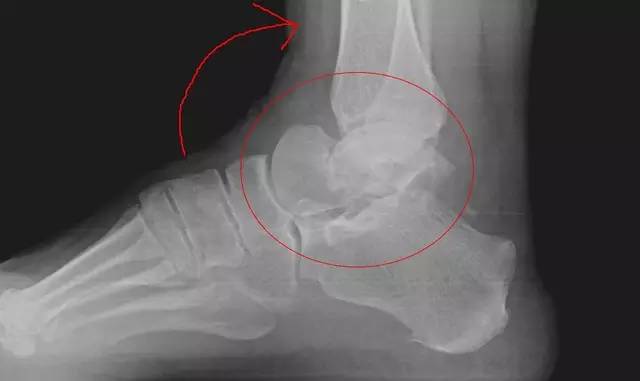

6. Pilon 骨折

涉及负重关节面(胫距关节面)与胫骨远侧干骺端的骨折。其典型特征是干骺端存在不同程度的压缩、干骺端的压缩粉碎性骨折不稳定、原发性关节软骨损伤以及永久性关节面不平整导致预后不良。

pilon 骨折正位片

pilon 骨折侧位片

pilon 骨折三维 CT 表现